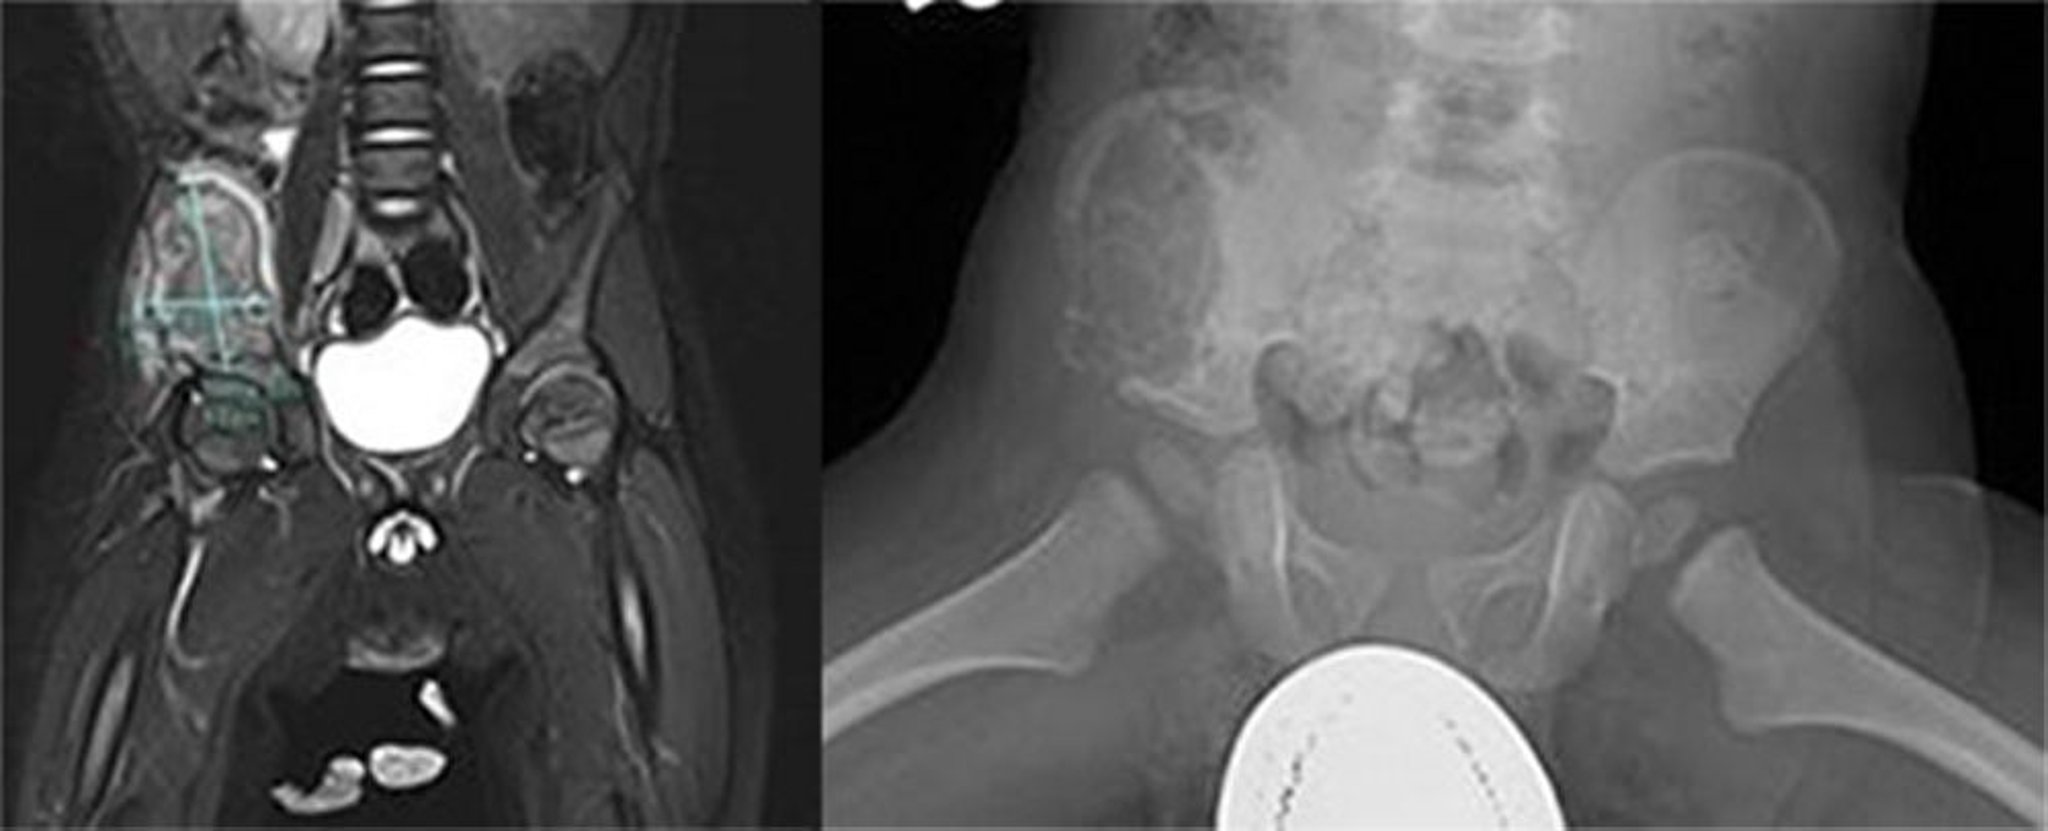

Bệnh mô bào Langerhans (xương chậu)

Hình ảnh này cho thấy một tổn thương lớn tích cực bên trong cánh chậu phải. Chụp MRI cho thấy khối không đồng nhất trên T2 và tín hiệu T1 thấp với sự tăng cường không đồng nhất của khối và các cơ xung quanh với sự lệch của cơ psoas bên phải về trung gian, gợi ý một tổn thương xương tích cực (bên trái). Một tổn thương màng cứng lớn trong ala phía trước và bên của hồi tràng kéo dài ra phía trước và phía dưới đường đẳng có thể nhìn thấy trên phim chụp X-quang (bên phải). Có vỏ não mở rộng và các bất thường về vỏ não. Sinh thiết là chẩn đoán cho bệnh mô bào tế bào Langerhans.

Hình ảnh do bác sĩ Carolyn Fein Levy và bác sĩ, tiến sĩ Jeffrey M. Lipton cung cấp.